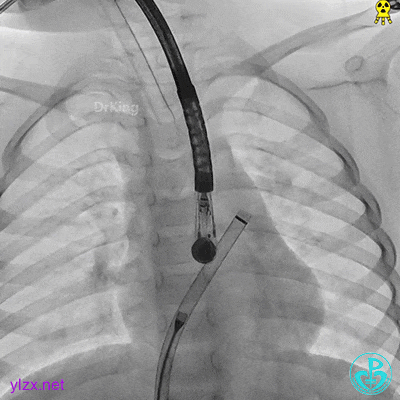

封堵器锁定

锁定后,主动脉短轴切面显示封堵器呈Y字型抱住主动脉根部。

牵拉稳定,锁定成功。

牵拉试验,封堵器位置固定,未见明显位移及形变。

完全释放后超声下观察

主动脉短轴切面显示封堵器呈Y字型抱住主动脉根部,夹持稳定。

封堵器形态良好,未见分流,封堵成功。